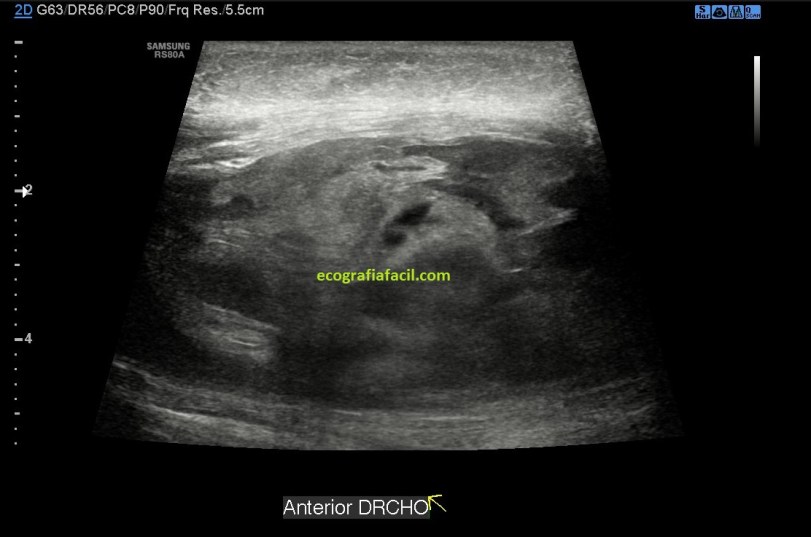

Se objetiva una imagen heterogénea e hipoecogénica de aspecto ovalado y parece corresponder a un hematoma probablemente intramuscular. En la imagen puedes observar lo que son fibras musculares de aspecto demasiado hipoecogénicas que no son compatibles con la normalidad a ese nivel como podría ser esta imagen siguiente, mira:

Sin ser una imagen maravillosa, la 5, ejemplifica claramente lo que es el aspecto normal del tejido muscular, que no tiene nada que ver en absoluto con la semiología de las imágenes 1 a 4, intuyéndose en estas imágenes (1 a 4), tejido muscular excesivamente hipoecogénico y aumentado de tamaño, así que me gustaría que perdieses tiempo en comparar tejido muscular normal con tejido muscular afectado por un hematoma.